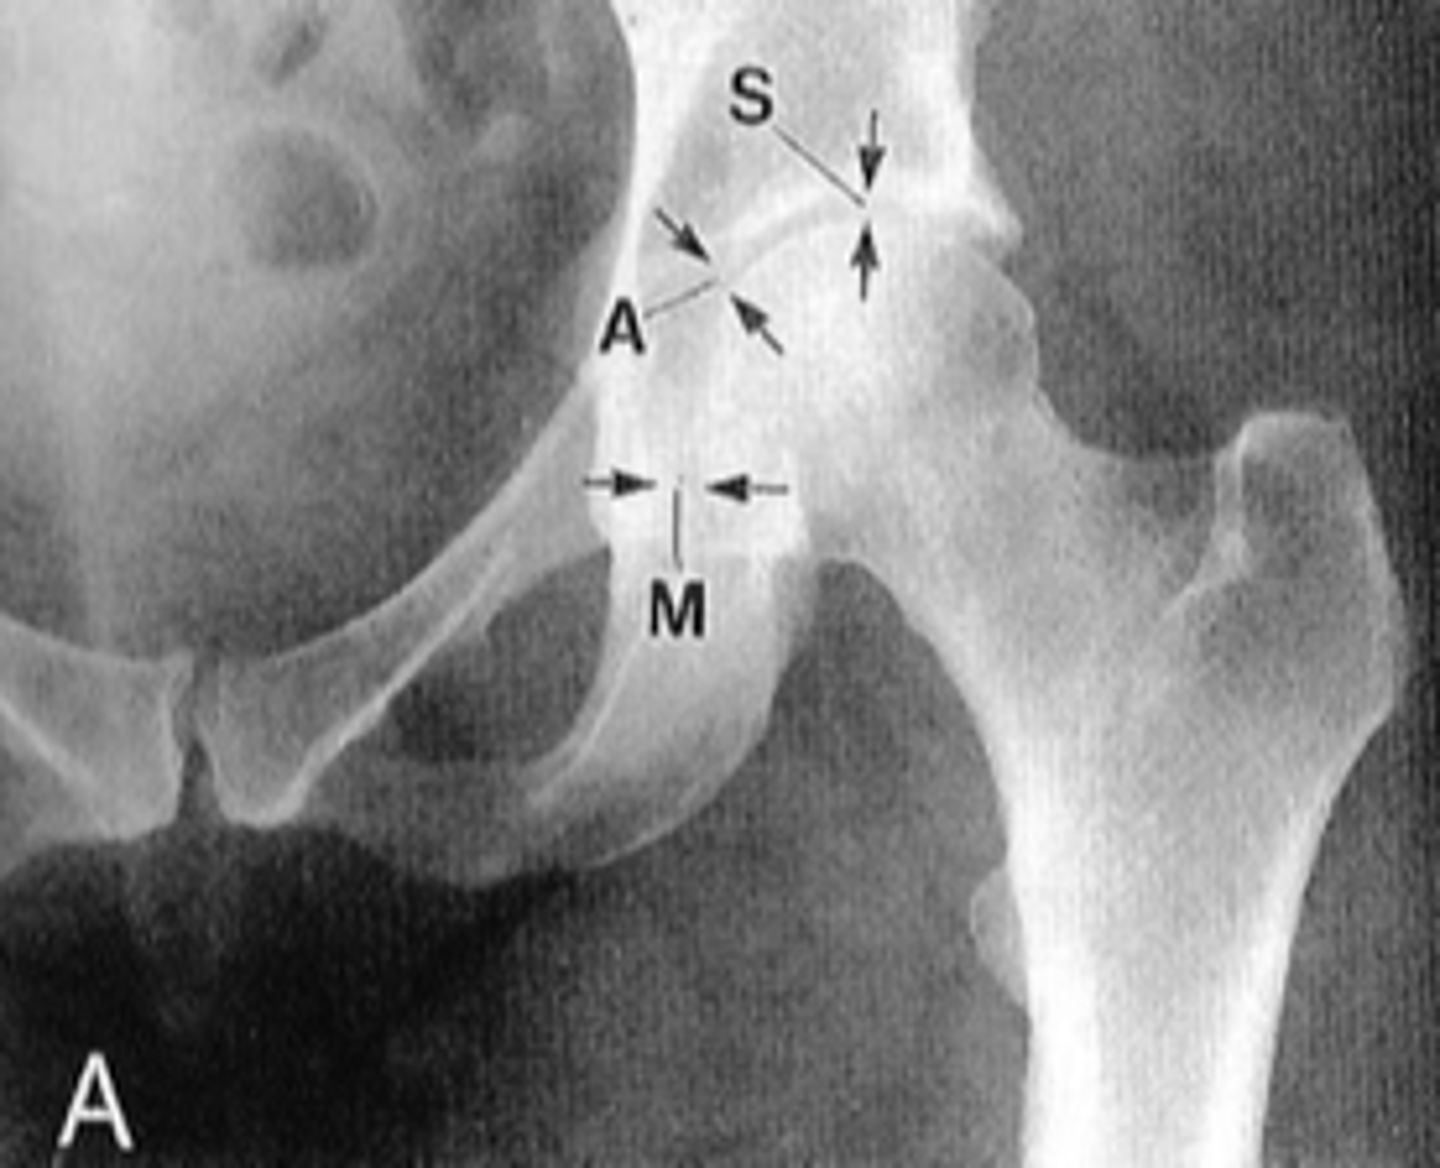

Pubic symphysis

ID 1

<p>ID 1</p>

Left femoroacetabular joint

ID 2 (joint)

<p>ID 2 (joint)</p>

Left posterior sacroiliac joint

ID 3 (joint)

<p>ID 3 (joint)</p>

Left anterior sacroiliac joint

ID 4 (joint)

<p>ID 4 (joint)</p>

Kohler's teardrop distance

ID measurement line

<p>ID measurement line</p>

- Medial margin of femoral head

- Lateral border of teardrop

Kohler's teardrop distance landmarks

6-11 mm

Normal Kohler's teardrop distance measurement

<p>Normal Kohler's teardrop distance measurement</p>

2 mm

The normal Kohler's teardrop distance is 6-11 mm, and there should be no greater than a _____ difference when comparing to the contralateral side

<p>The normal Kohler's teardrop distance is 6-11 mm, and there should be no greater than a _____ difference when comparing to the contralateral side</p>

Hip joint effusion

Clinical significance of an enlarged Kohler's teardrop distance

<p>Clinical significance of an enlarged Kohler's teardrop distance</p>

Waldenstrom's sign

What sign indicates an enlarged Kohler's teardrop distance?

- Accentutation of the normal limits

<p>What sign indicates an enlarged Kohler's teardrop distance?</p><p>- Accentutation of the normal limits</p>

Intracapsular swelling/joint effusion

Waldenstrom's sign is usually an indication of _____

<p>Waldenstrom's sign is usually an indication of _____</p>

Inflammatory arthritis

Clinical significance of a small Kohler's teardrop distance

<p>Clinical significance of a small Kohler's teardrop distance</p>

Hip joint space width

ID measurement

<p>ID measurement</p>

Superior, axial, medial joint spaces (SAM)

Hip joint space width landmarks

<p>Hip joint space width landmarks</p>